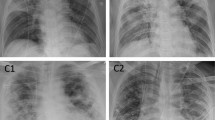

Example cases of patients with pneumonia. (a) A patient with a CURB-65 of 2 and PSI of 97 had an initial O2 requirement of 6L, no intubation, and an AI-based consolidation score of 96% on the initial CXR. This patient died during admission for pneumonia treatment. (b) A patient with a CURB-65 of 1 and PSI of 117 had an initial O2 requirement of 2L, no intubation, and a consolidation score of 40% on the initial CXR. This patient recovered and was discharged after treatment. CURB-65, confusion, urea, respiratory rate, blood pressure, and age ≥ 65; CXR, chest radiograph; PSI, pneumonia severity index; Csn, consolidation.